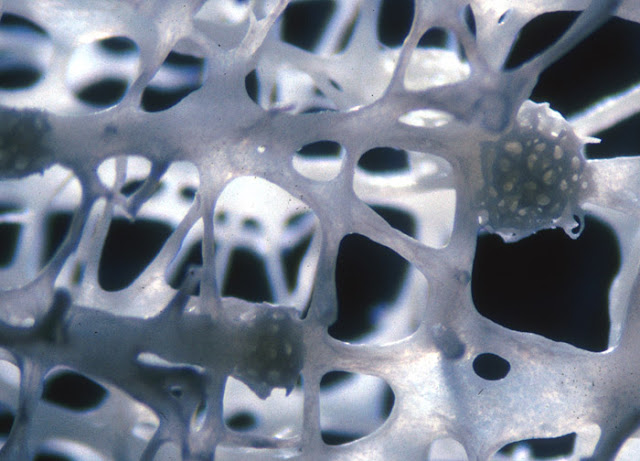

Osteoporosis in vertebra showing 3 microfractures 椎體骨質疏鬆症

Specimen: Osteoporosis in vertebra showing 3 microfractures

Technique: Polarized light, 15x Objective